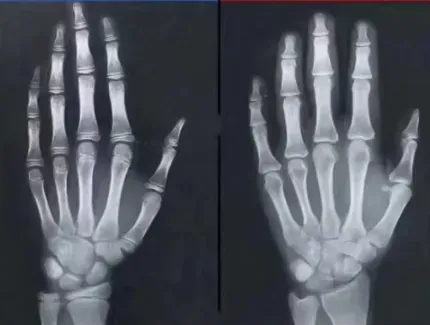

孩子还能不能长高,主要可以看孩子的骨骺线有没有闭合。家长们可能对骨骺线并不是很了解。

骨骺线是骨骺与干骺端之间的软骨,在幼儿X光片上表现为一条较宽的透光带,它随着年龄的增长而逐渐变短,当骨骺与干骺端的软骨完全骨化后,就形成一条紧密的缝,此时骨骺线完全闭合,骨骼停止生长。

当然,骨骺线闭合并不意味着这块软骨变薄,而是随着年龄增长,这块软骨会逐渐骨化,当它完全骨化之后,长骨就没有多少生长空间了,随即骨骼生长也就停止了。

这也代表孩子的身高基本定型了,基本上不会再长高了。

想要知道自家孩子的骨骺线是否闭合,孩子还能不能再继续长高,可以在医院进行骨龄检查,通过左手x光图像,可以查看骨骺线是否闭合。

如果还没完全闭合,那就还有继续长高的机会,抓紧时机“蹿一蹿”,孩子还能再长高。抓住闭合前信号,孩子还能再长高!